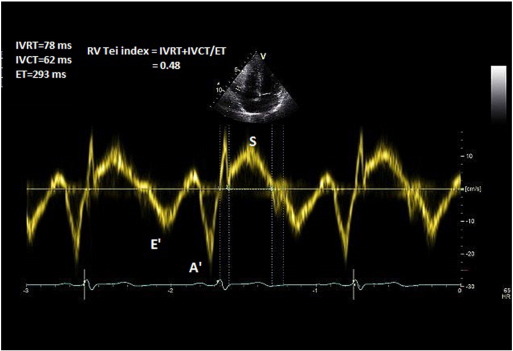

In the apical 4-chamber view, TDI is deployed on the RV free wall and a 3–5 mm pulse wave Doppler is obtained approximately 1 cm from the tricuspid annulus. Isovolemic contraction time (IVCT), isovolemic relaxation time (IVRT), and ejection time (ET) of the RV are then measured (Fig. 8 ). Alternatively, these measures could be obtained from CW Doppler across the RV inflow/TR jet. Tei index is measured by the formula: Tei Index (RV) = IVRT + IVCT/ET.

Fig. 8. Measurement of Tei index. |

The method was studied in small groups of patients and has not yet been validated in larger sample sizes [28] and [29] . Tei index is, however, proven to prognosticate patients with pulmonary hypertension [30] .